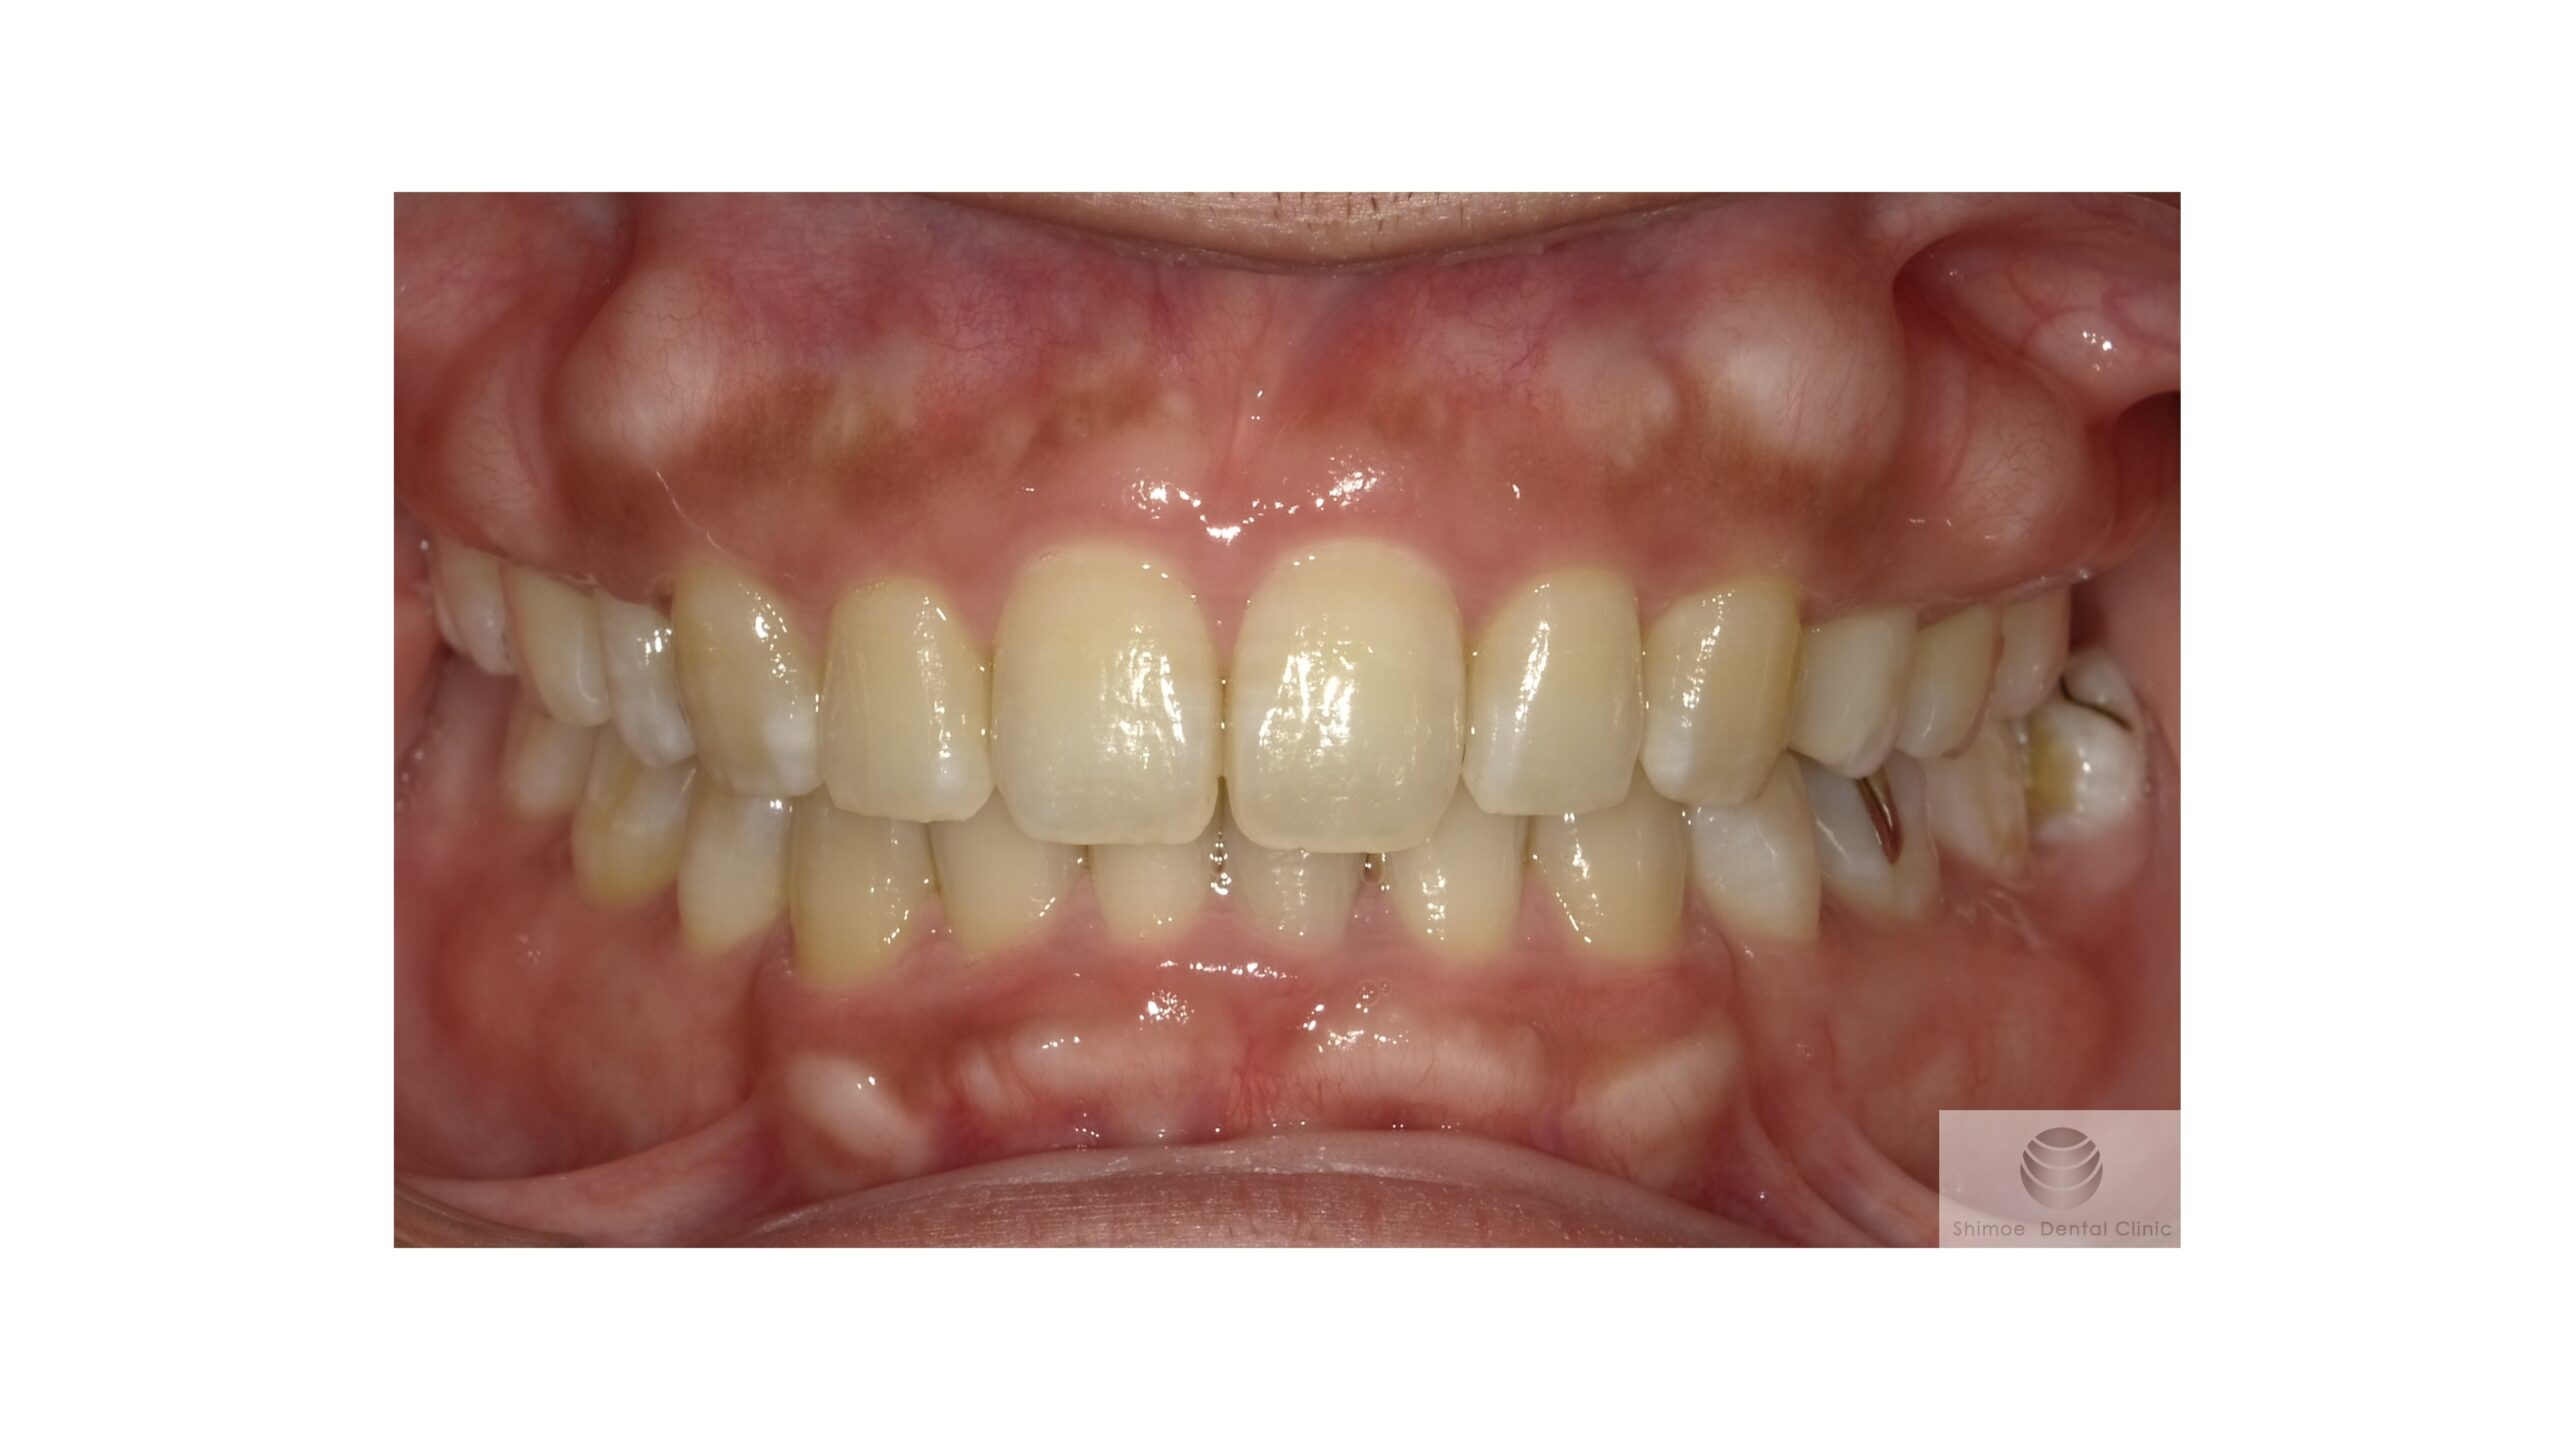

術後8か月

術後8か月経過 口腔内写真

経過は非常に良好です。

当初は下顎の骨隆起と上の奥歯の骨隆起についても手術をご希望されていましたが、上顎の凸凹した骨隆起が無くなったことで見た目の印象が良くなり、審美的にも満足され、下顎および上顎奥の骨隆起は気にならなくなられました。そのため下顎と上顎の奥歯の手術は行っていません。